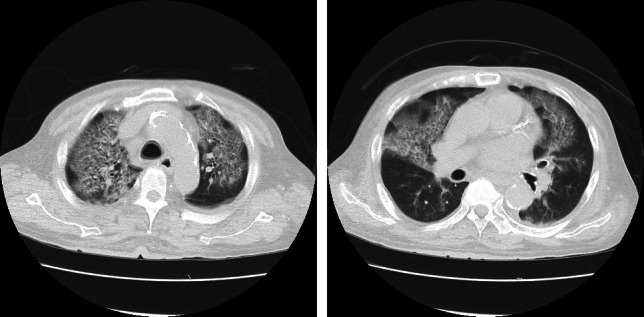

Seasonal influenza is prevalent globally, particularly during winter months. It is well documented that this disease causes severe, often fatal complications in hemodialysis patients. While numerous reports have focused on novel influenza viruses, there is a paucity of case reports detailing seasonal influenza viral infections in this patient population. This case presents a 71-year-old male undergoing hemodialysis who developed severe seasonal influenza A pneumonia despite receiving the influenza vaccine and early antiviral treatment. Initially presenting with fever, cough, and myalgia, the patient was diagnosed with influenza A virus infection and hospitalized due to heightened risk associated with dialysis and an elevated inflammatory response. Despite treatment with two different antiviral medications, his condition deteriorated, leading to ARDS (acute respiratory distress syndrome). The administration of steroid pulse therapy resulted in significant clinical improvement. This case underscores the severe nature of influenza virus-related illnesses in dialysis patients, even with vaccination and early antiviral intervention. It also suggests the potential benefit of early steroid pulse therapy in managing severe influenza pneumonia in high-risk individuals.